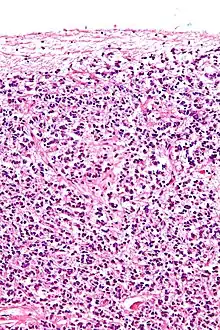

Pinealócitos têm grandes núcleos irregulares com nucléolos proeminentes.